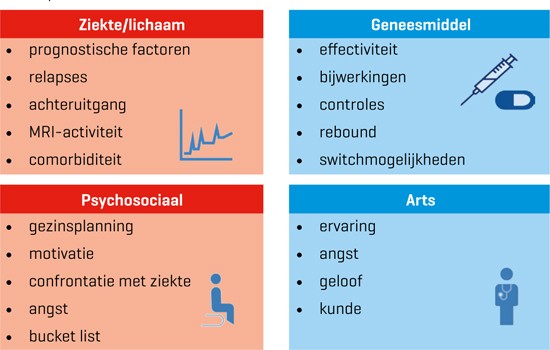

De keuze voor een bepaald middel kan afhangen van medische factoren (ziekteactiviteit), persoonlijke factoren (kinderwens, comorbiditeit) en psychologische factoren (IRT kan patiënten aanspreken die liever niet continu medicatie willen slikken, en patiënten juist afschrikken die onrustig worden van ‘niets doen tot de ziekte misschien terugkomt’ [figuur 2]). Het starten en kiezen van de behandeling is dan ook een zaak van gezamenlijke besluitvorming. In onze casus volgde de behandeling de principes van stepped care. Kort na de diagnose startte Piet met glatirameeracetaat. In de jaren daarna had hij nog regelmatig terugvallen waarvoor behandeling noodzakelijk was. Dit, en het feit dat ook de MRI toenemende afwijkingen toonde, was reden om over te gaan naar natalizumab. Sindsdien zijn er geen duidelijke terugvallen of veranderingen op MRI geconstateerd.

Figuur 2 | De factoren die bij gezamenlijke besluitvorming de behandelkeuze bij MS bepalen